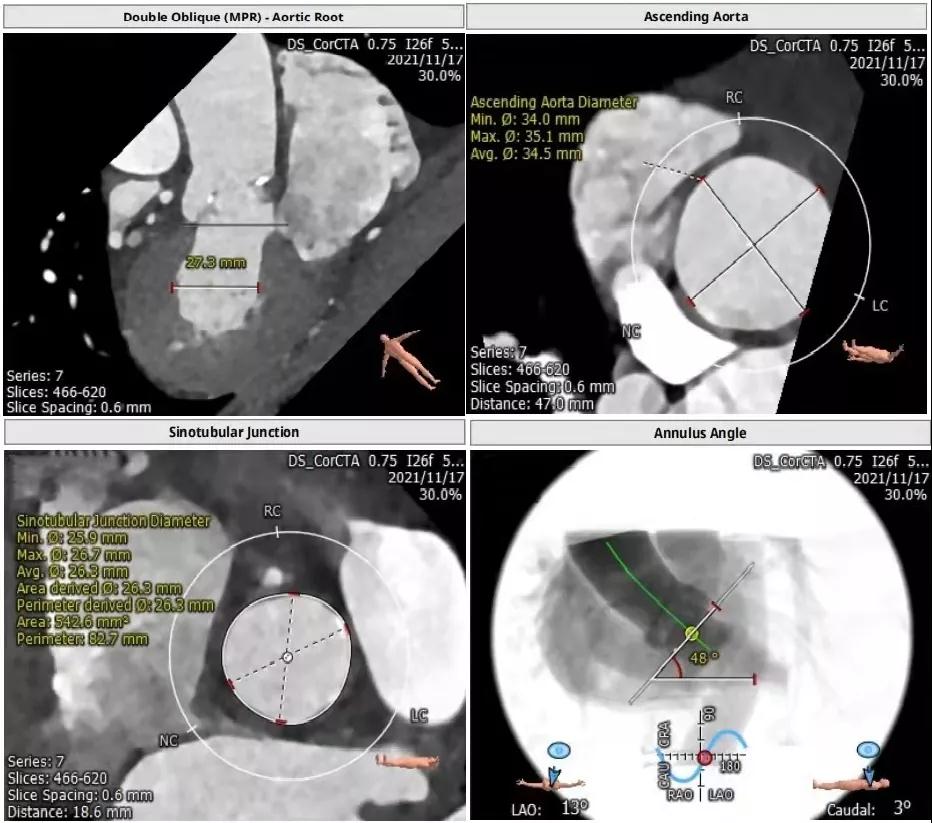

主动脉瓣CT评估:

三叶瓣,瓣环直径22.4mm,瓣环长短径分别为25.0*20.0mm,周长为70.4mm,面积为383.4mm²。左室流出道直径21.8mm,瓦式窦31.7mm*30.2mm*30.6mm,左冠高度11.1mm,右冠高度15.3mm,窦管交界直径26.3mm。

根部解剖: